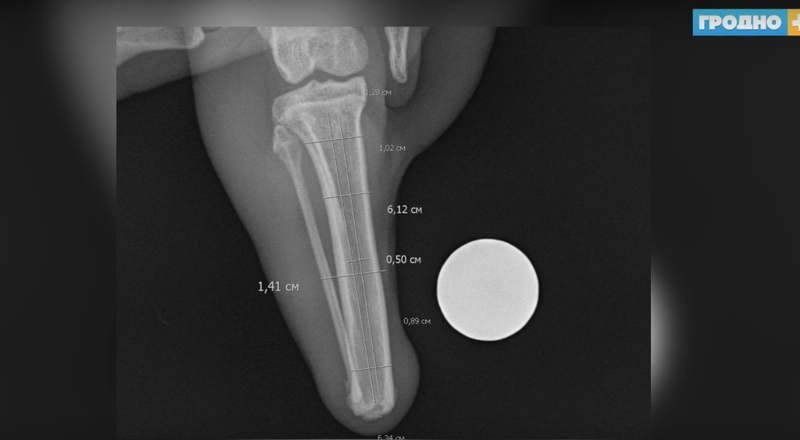

По заказу лидского коллеги в Новосибирске при помощи 3D-принтера изготовили протез. Изделие состоит из сплава титана и гидроксиапатита. Весит всего несколько граммов. Сейчас необходимо некоторое количество времени, чтобы протез вжился в кость, и чтобы произошла полная интеграция живого и искусственного материала. Операция проходила в несколько этапов. Первый из них — сделать доступ из старой культи, поскольку травма уже имела свой срок давности.

«Крайне важно было рассверлить кость настолько правильно, чтобы в идеале имплант мы не раскололи. Это был самый сложный этап операции, поскольку говорим про размеры крайне небольшие. Это порядка 0,5-0,6 см», — рассказывает Павел Жульпа, главный ветеринарный врач ветклиники города Лиды. «Затем мы выполнили имплантацию данного импланта. Затем стабилизацию и после этого ушили культю. Ушивание культи тоже было трудоёмким процессом, поскольку мягкие ткани тоже являются основными осложнениями при протезировании протезами».